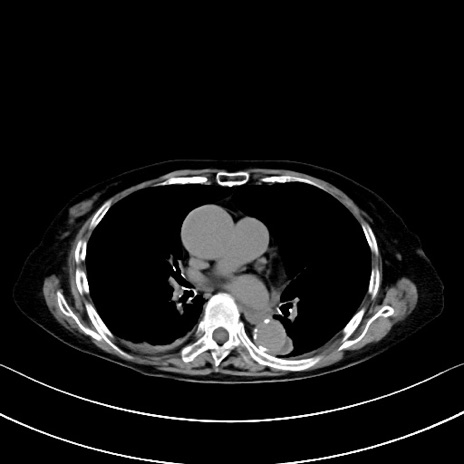

症例40(横断像)他院1日前

横断像

他院CT